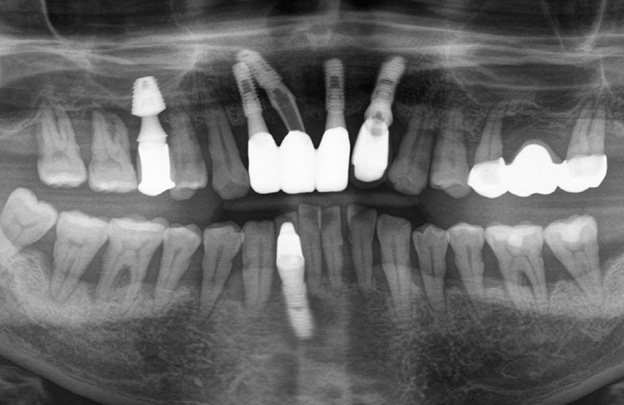

전체 임플란트 증례

BEFORE

AFTER

임플란트 촬영날짜: 2021-12-31

임플란트 촬영날짜: 2021-11-09

전체 임플란트 촬영날짜: